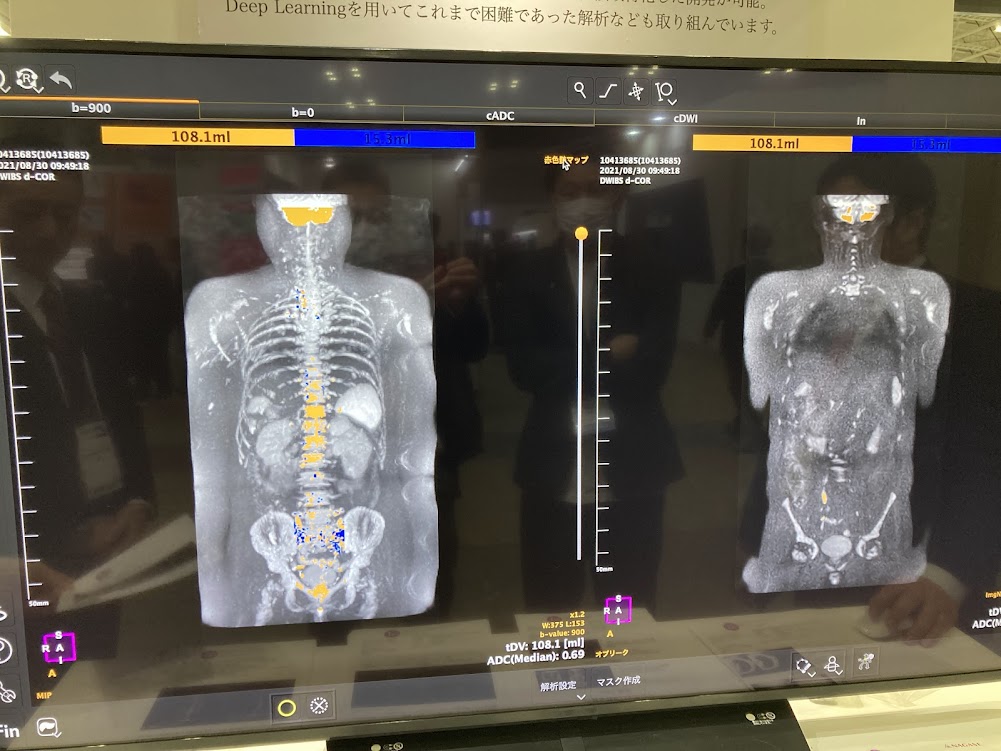

医療用3Dワークステーションで学ぶ 脳神経外科手術戦略。医療用3Dワークステーションで学ぶ 脳神経外科手術戦略。脳神経外科 Vol.50 No.4: STA-MCAバイパス術―日本が世界に誇る技。パックご飯秋田米100%。大阪公立大学大学院医学研究科 脳神経外科学教室とコラボ 新しい。タグ「Opening the future ~医用画像処理のネクストステージ。医療用3Dワークステーションで学ぶ脳神経外科手術戦略シミュレーションこちらは裁断済みの商品です。定価:11000円。ITEM2024レポート 〜Workstaion編〜 | MRIfan.net。教科書『Robotic Surgery Devices in Surgical Specialties。ziostation2 | アミン株式会社。ムービーコンテンツ – AESCULAP® Orthopaedic Academy online。ITEM2024レポート 〜Workstaion編〜 | MRIfan.net。。ITEM2024レポート 〜Workstaion編〜 | MRIfan.net。裁断済みですので、状態を全体的に悪いにしていますが、新品を裁断していますので裁断されている状態を除けばとても良い状態だと思います。第18回日本整容脳神経外科学会(JSAN2025)/第34回脳神経外科